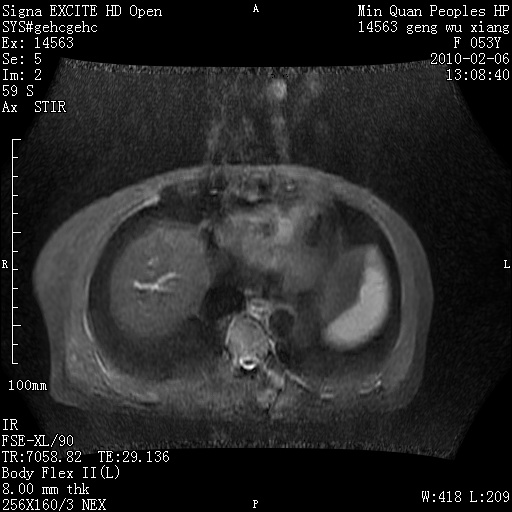

标题: MRI2762:胆道梗阻原因?

f,53y,全身黄染多日。

高位胆道梗阻 胆管癌可能性大

支持 高位胆道梗阻 胆管癌可能性大。